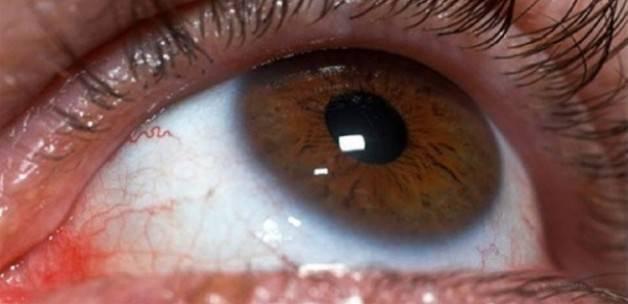

göz akının sararması

Göz akının sararması. Yani vücutta tene rengini veren göz zarında da bulunan melanin pigmenti miktarı artarsa göz akında sararmalar görülebilir. Havuç ıspanak lahana portakal ve sarı renkli meyvelerdir. Kan bilindiği gibi pek çok farklı maddeden oluşmakta ve bu maddelerden biri olan biliruibinin fazlalığı halinde gözde sararma meydana gelmektedir. Göz akının sararması neden olur.

Genel olarak tek başında görülmeyen bir durum olan göz akı sararması bir hastalığım belirtisi olarak bizleri uyarmaktadır. Aslında sarılık hastalık değil birçok durumda ortaya çıkabilen bir belirtidir. Zamanla güneş ışınlarının etkisi ile de sklerada melanin pigmenti birikmesi ile oluşur. Fakat melanin miktarı fazla artıp ben oluşumuna neden de olabilir.

Kanda bilüribin denilen bir maddenin artması nedeniyle göz ve cildin sararmasıdır. Göz akında oluşan sararma fizyolojik olabileceği gibi patolojik de olabilir. Bir doktor enzim eksikliğinden dedi. Göz akının sararması merhaba hocam gözlerimin akı öncelere göre sarardı bembeyaz durmuyor bu durum beni rahatsız ettiğinden birkaç kez doktora gittim ancak her seferinde 15 günden fazla kullanmamamı söylediği damlalar verdi.

A vitamini göz için çok yararlı olacaktır. Ama sarılık hastalığı yok. Adet döneminde sarılar o zaman artıyor. Sklerada oluşan sararmalar zamanla oluşabilir.